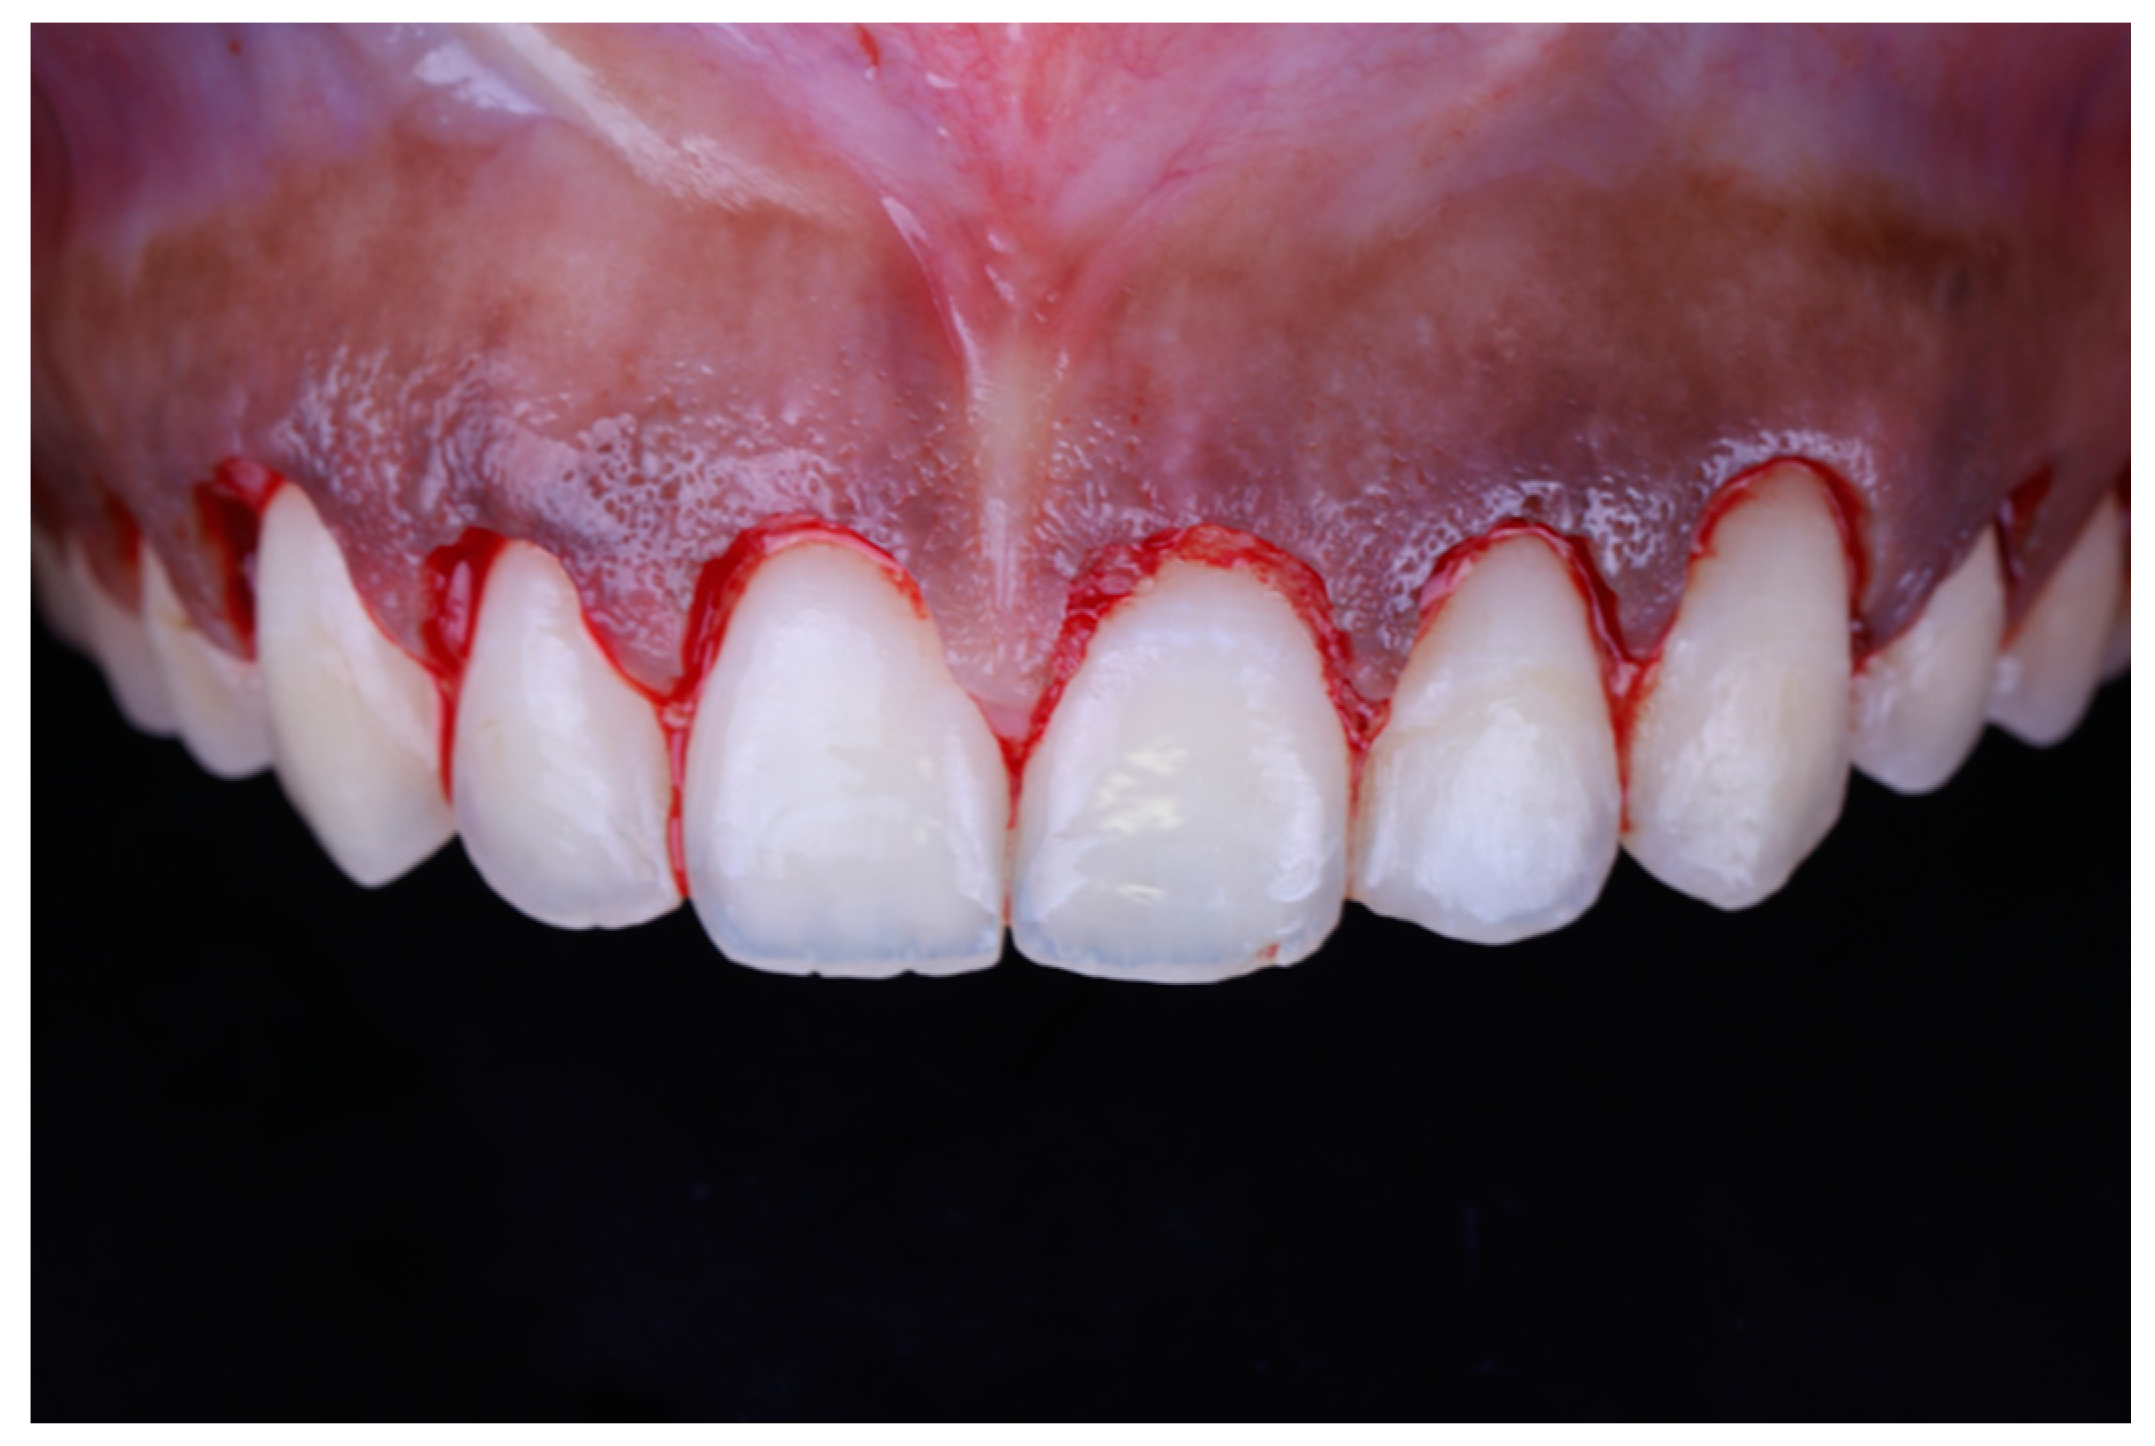

Local anesthesia (xylocaine with epinephrine 1:100.000) was administered via buccal infiltration. The guide was then placed. Using a 15c blade and following the upper border of the window of the guide, an internal bevel incision was made from right to left first molar teeth (Figure 5). The guide was then removed and a second incision was made in a sulcular fashion. The secondary flap was removed using a Youger-Good curette while visualizing the new crown lengths (Figure 6).

Figure 5.

Surgical incision based on the guide.

Figure 6.

Tooth length after gingival excision.